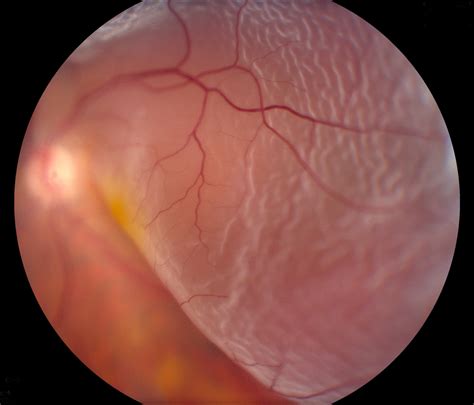

Retinal detachment is a serious medical condition that occurs when the retina, the light-sensitive layer of tissue at the back of the eye, separates from its underlying support tissue. This condition can lead to permanent vision loss if not treated promptly. Understanding the various retinal detachment causes is crucial for early detection and effective management. This blog post delves into the different factors that contribute to retinal detachment, its symptoms, diagnosis, and treatment options.

Physical injury to the eye, such as a blow to the head or a penetrating injury, can cause retinal detachment. Trauma can lead to the formation of retinal tears or holes, which allow fluid to accumulate behind the retina, causing it to detach.

• Retinal Tears or Holes: These can occur due to various reasons, including age-related changes, trauma, or underlying medical conditions. Fluid can seep through these tears or holes, causing the retina to detach.

• Shadows or Curtain-Like Vision Loss: A dark shadow or curtain that seems to cover part of your visual field.